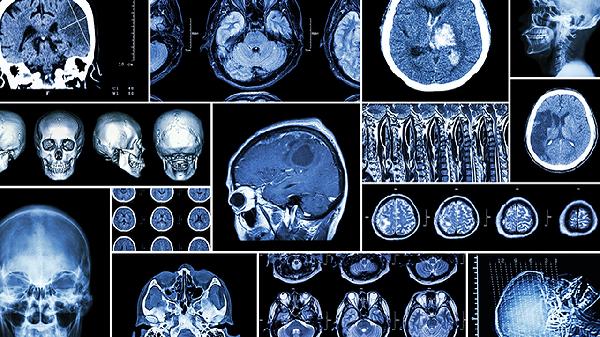

查脑血栓做什么检查 查脑血栓必做检查盘点

查脑血栓需要做头部CT、头部磁共振成像、脑血管造影、颈动脉超声、经颅多普勒超声等检查。脑血栓通常由动脉粥样硬化、高血压、糖尿病等因素引起,可能伴随肢体麻木、言语不清、头晕等症状。

头部CT是诊断脑血栓的常用检查方法,能够快速显示脑部出血和缺血性病变。脑血栓在CT上表现为低密度影,发病早期可能显示不明显,需结合临床症状判断。头部CT检查无创且耗时短,适合急诊筛查。对于疑似脑血栓患者,医生通常会优先安排头部CT检查以排除脑出血。

头部磁共振成像对脑血栓的诊断敏感性高于CT,特别是弥散加权成像能在发病后数分钟内显示缺血病灶。磁共振成像可清晰显示脑干、小脑等CT难以观察的区域,还能评估脑组织损伤程度。磁共振血管成像无需注射造影剂即可显示脑血管情况,但检查时间较长且费用较高。

脑血管造影是诊断脑血管病变的金标准,可清晰显示脑血管狭窄或闭塞部位。通过股动脉穿刺注入造影剂,能准确判断血栓位置和血管狭窄程度,为血管内治疗提供依据。脑血管造影属于有创检查,存在一定风险,通常在其他检查无法明确诊断时采用。